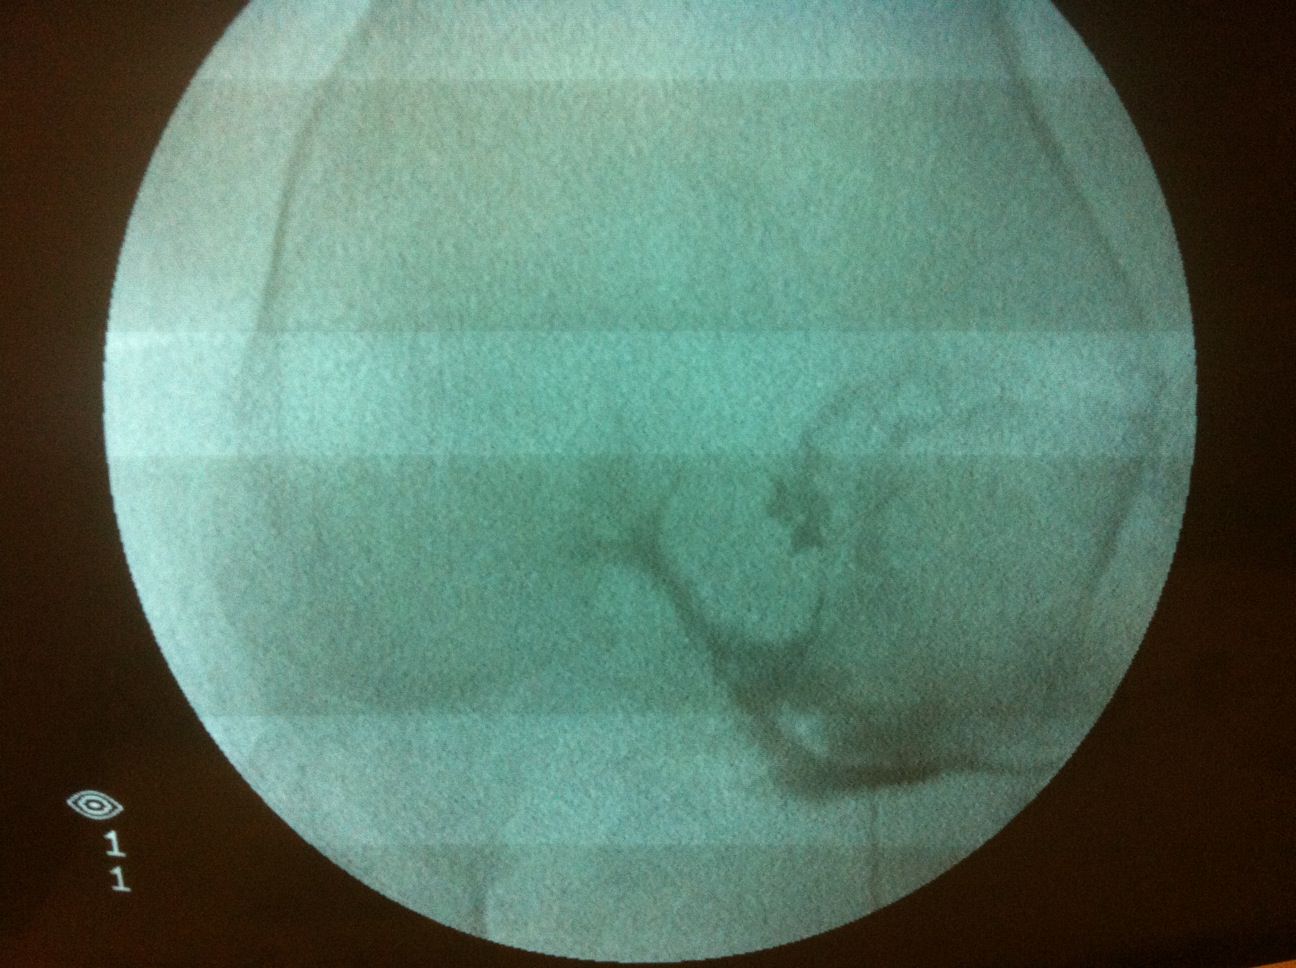

Une repérage de la zone à viscosupplémentée est réalisée sous radioscopie. Une arthrographie pré injection confirme le bon positionnement de l’aiguille en intra-articulaire et permet d’analyser l’articulation (capsulite rétractile, osteochondromatose etc…).

L’injection de viscosuppléant (acide hyaluronique) est réalisé sous scopie, une association avec un corticoide est possible.